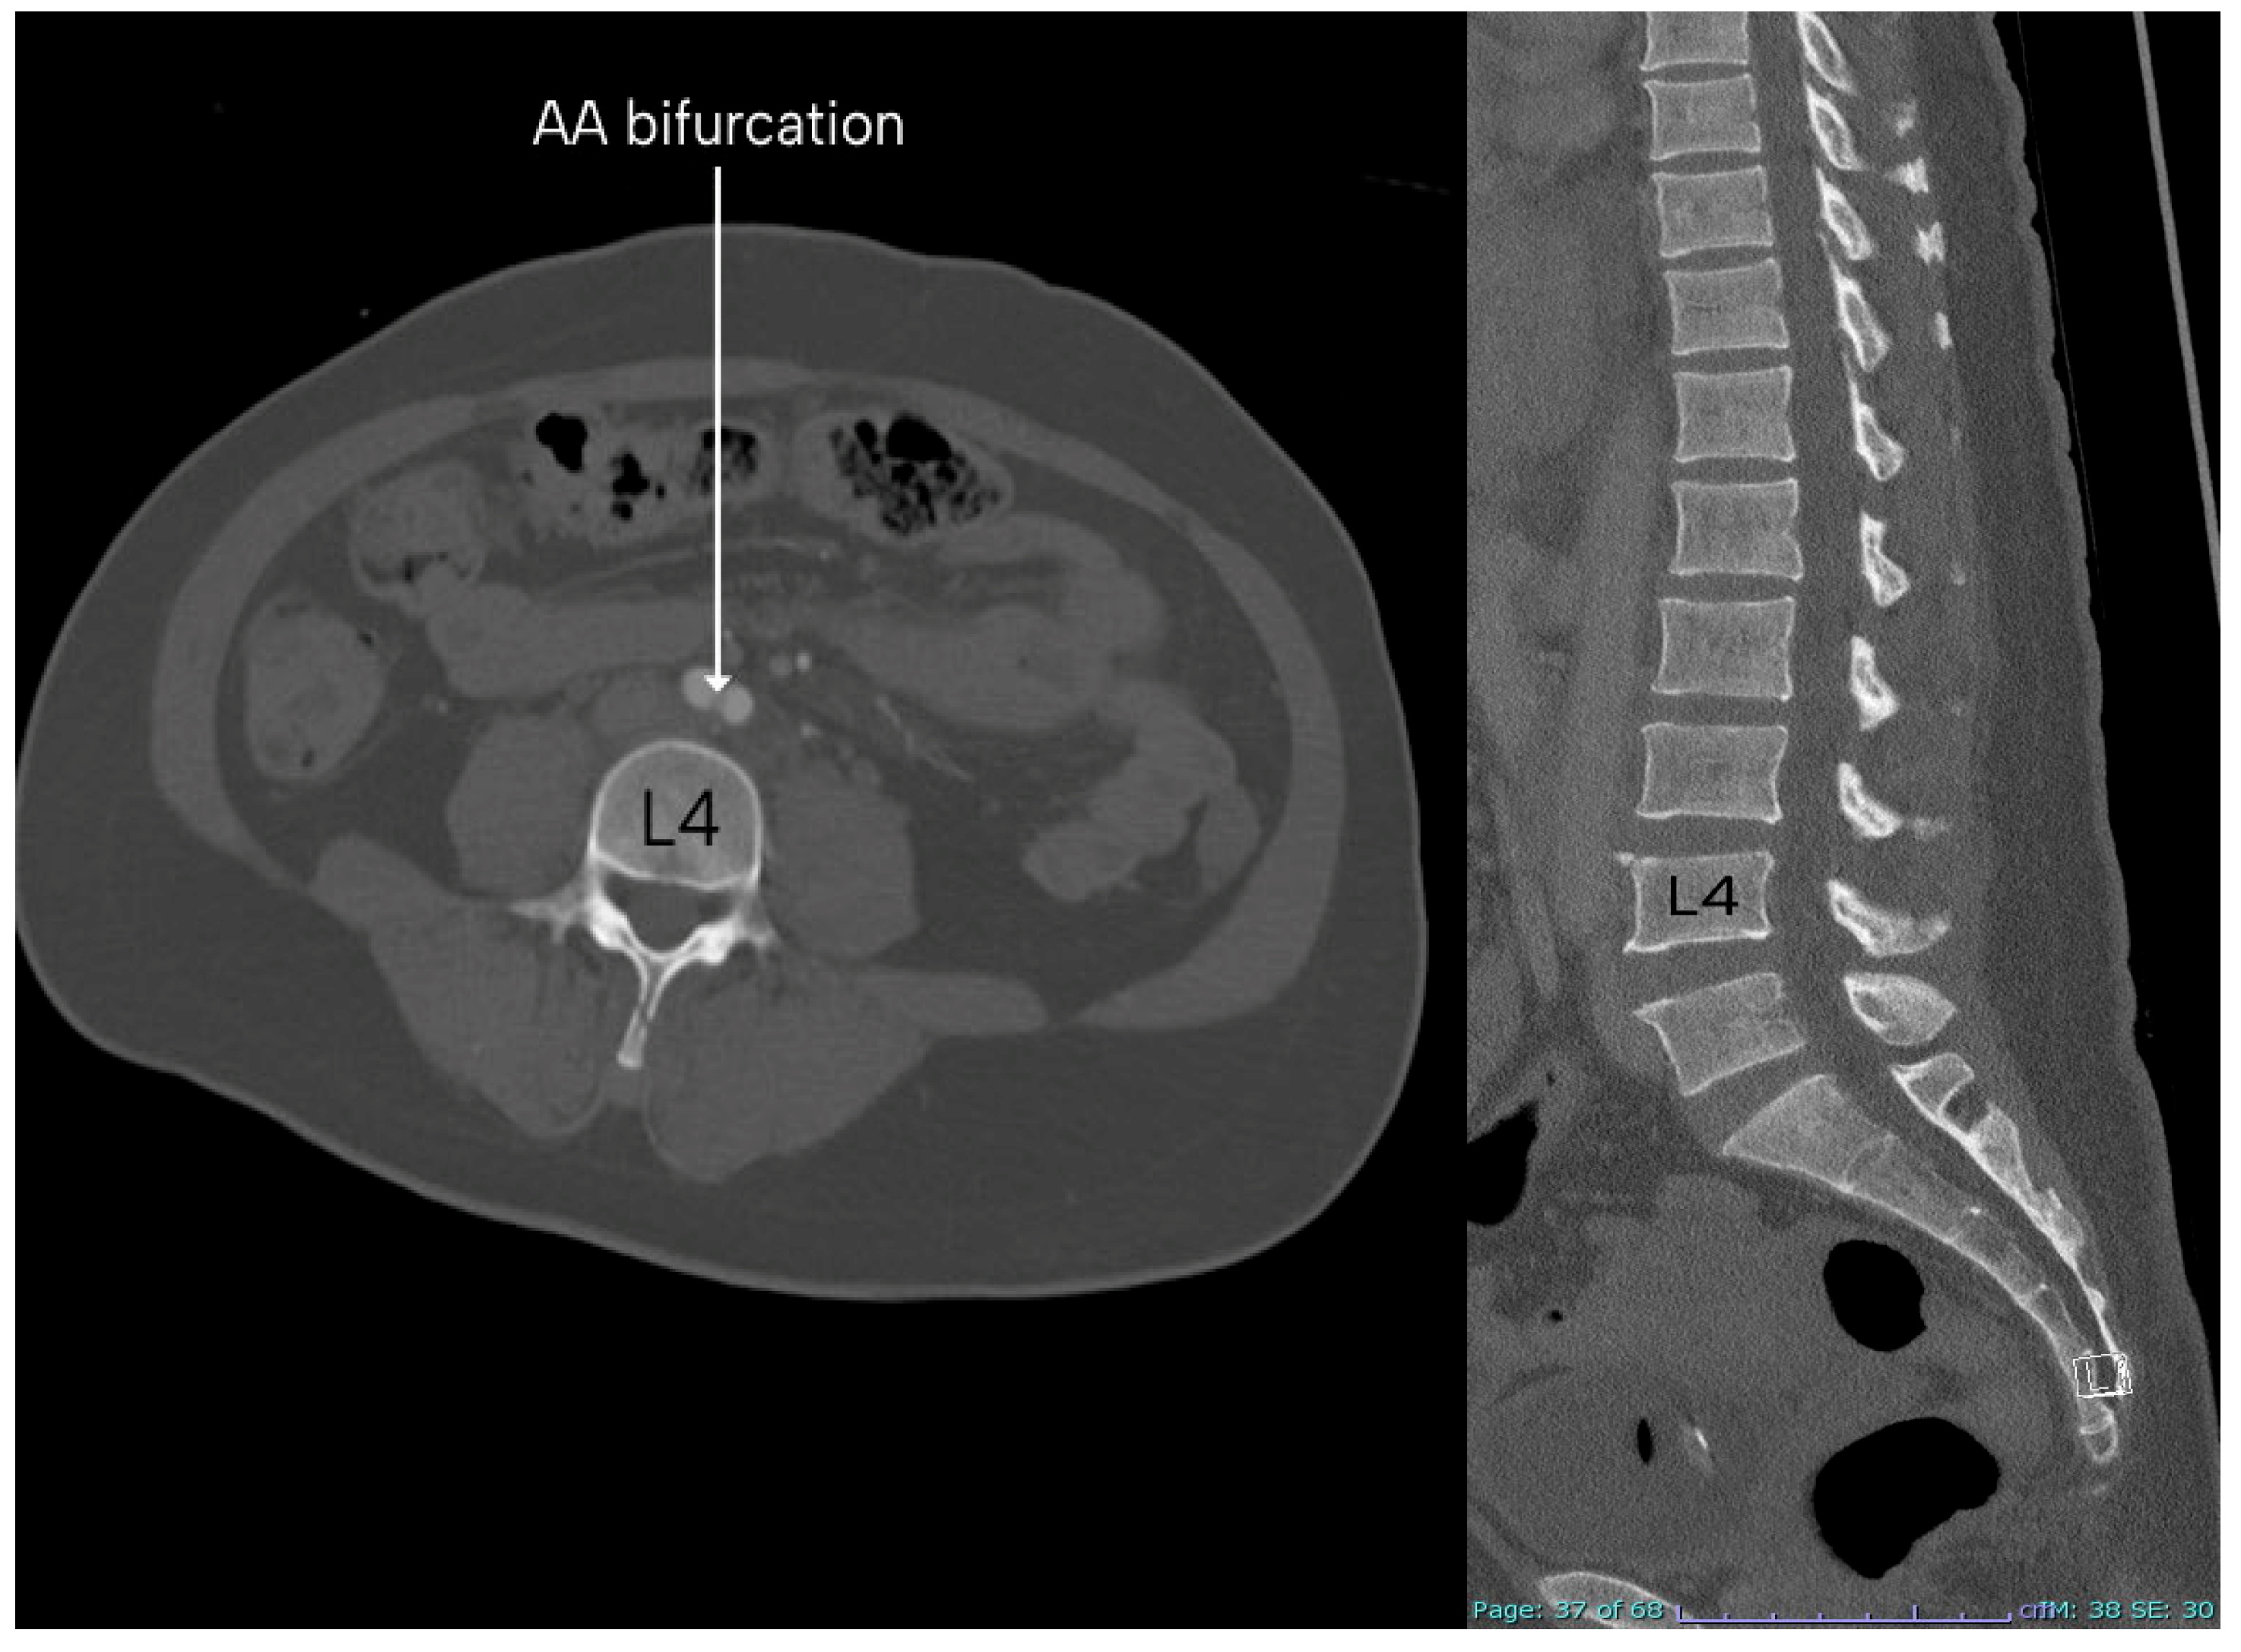

Level of Abdominal Aorta Bifurcation and Its Relation to the Ureter: A Radiological Study with Clinical Implications

3. Results

| Vertebral Level | Males | Females |

|---|---|---|

| L3 | 34 (23.61%) | 18 (32.14%) |

| L4 | 102 (70.83%) | 35 (62.50%) |

| L5 | 8 (5.56%) | 3 (5.36%) |

| Total | 144 (100%) | 56 (100%) |